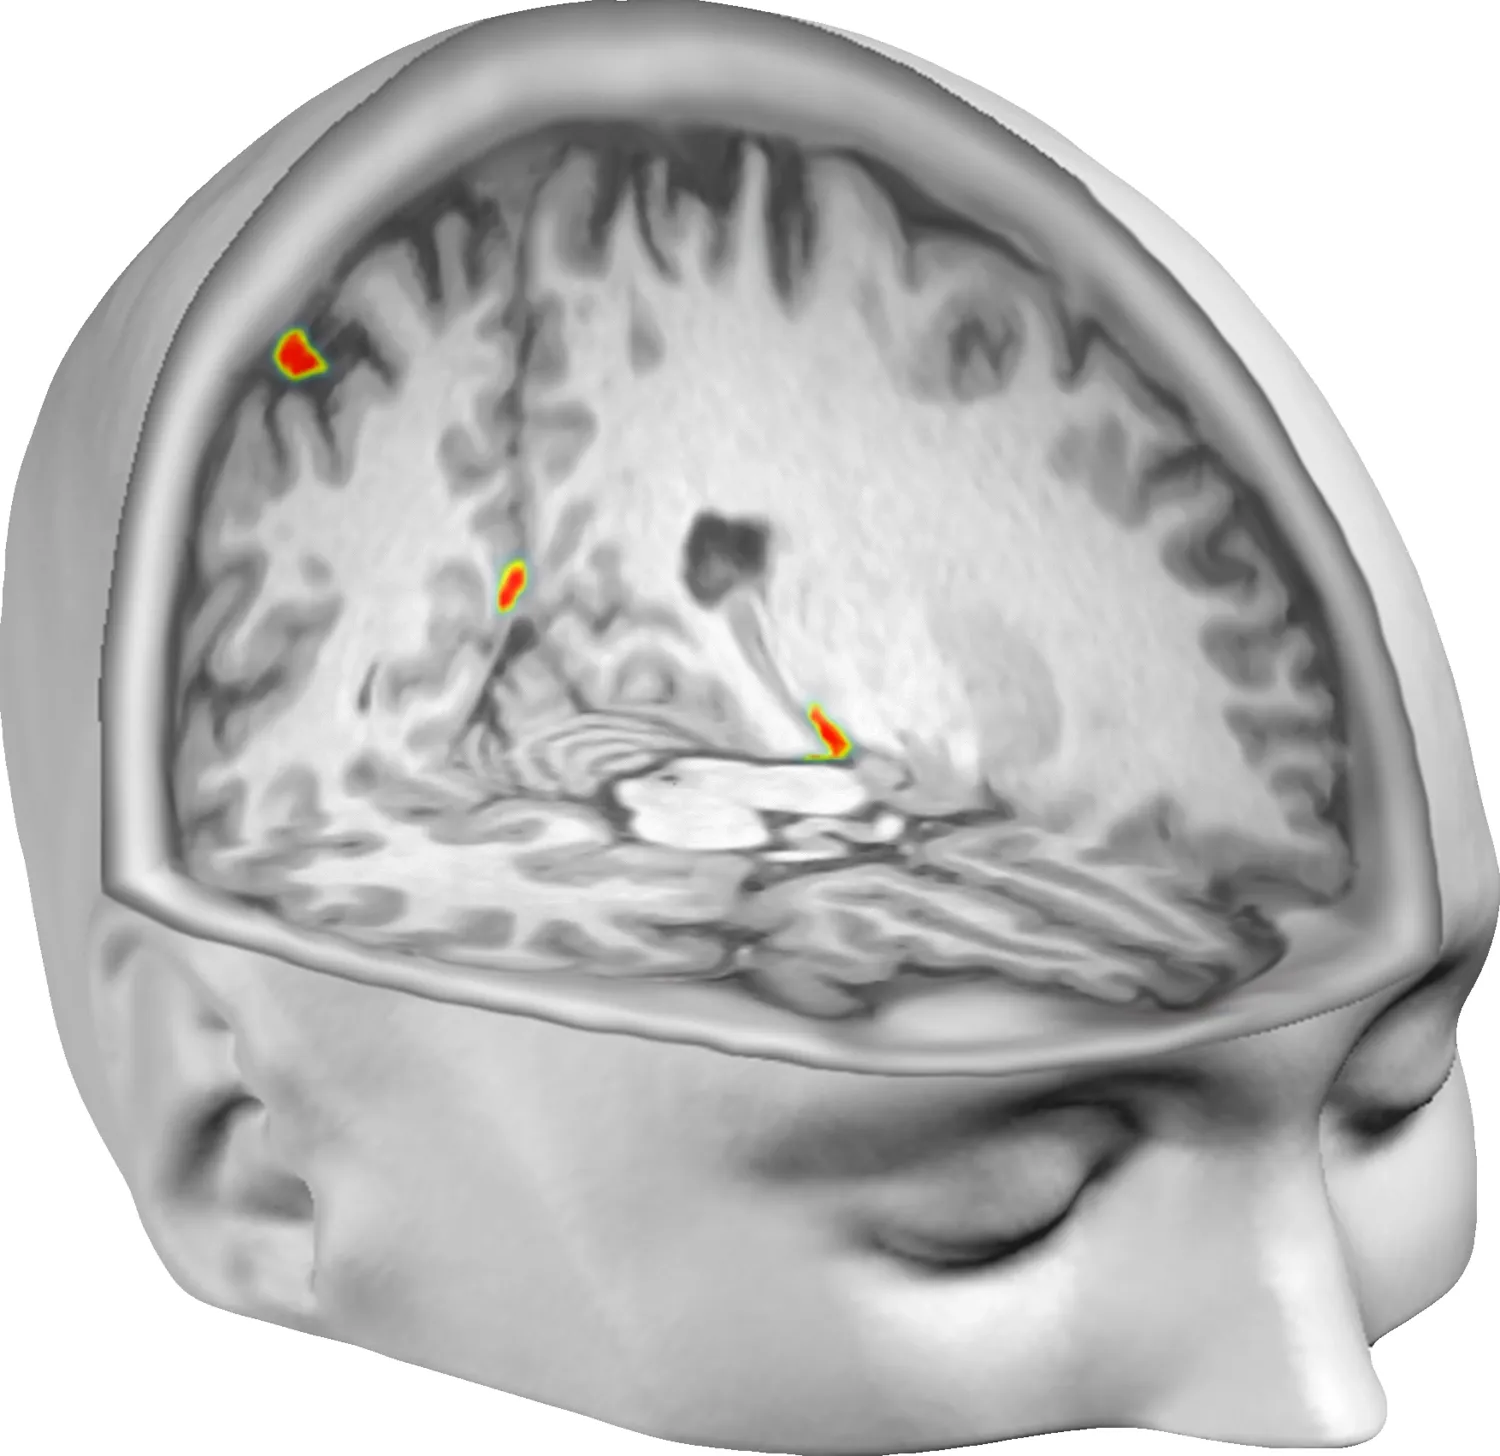

Combining behavioral and computational methods with functional magnetic resonance imaging (fMRI) has revealed how multisensory integration within premotor-posterior parietal and subcortical networks gives rise to body ownership, following probabilistic principles of perceptual inference. By integrating the spatial precision of fMRI with the millisecond temporal resolution of electroencephalography (EEG) and magnetoencephalography (MEG), we can characterize both where and when body-ownership computations occur in the brain. EEG experiments have shown that alpha-band oscillations constrain the temporal precision of sensory integration underlying bodily self-perception, while MEG has revealed how body-ownership-related activity patterns unfold dynamically across the brain with millisecond resolution.

Electrocorticography (ECoG), which provides high-quality neurophysiological signals from electrodes placed directly on the cortical surface in neurological patients, has linked the sense of limb ownership to increased high-gamma power—an index of local neuronal population firing—in premotor and posterior parietal cortex.

Our neuroimaging studies have also demonstrated that body ownership and self-location depend on two interacting systems: lateral fronto-parietal circuits supporting body ownership and medial parieto-retrosplenial-hippocampal circuits supporting bodily self-location. Together, these systems give rise to the “in-body” experience of being located within one’s own body at a specific position in space.